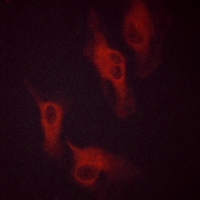

Immunofluorescent analysis of Beta-2 Adrenergic Receptor (Phospho-S346) staining in HeLa cells. Formalin-fixed cells were permeabilized with 0.1% Triton X-100 in TBS for 5-10 minutes and blocked with 3% BSA-PBS for 30 minutes at room temperature. Cells were probed with the primary antibody in 3% BSA-PBS and incubated overnight at 4 °C in a hidified chamber. Cells were washed with PBST and incubated with a AF594-conjugated secondary antibody (red) in PBS at room temperature in the dark.